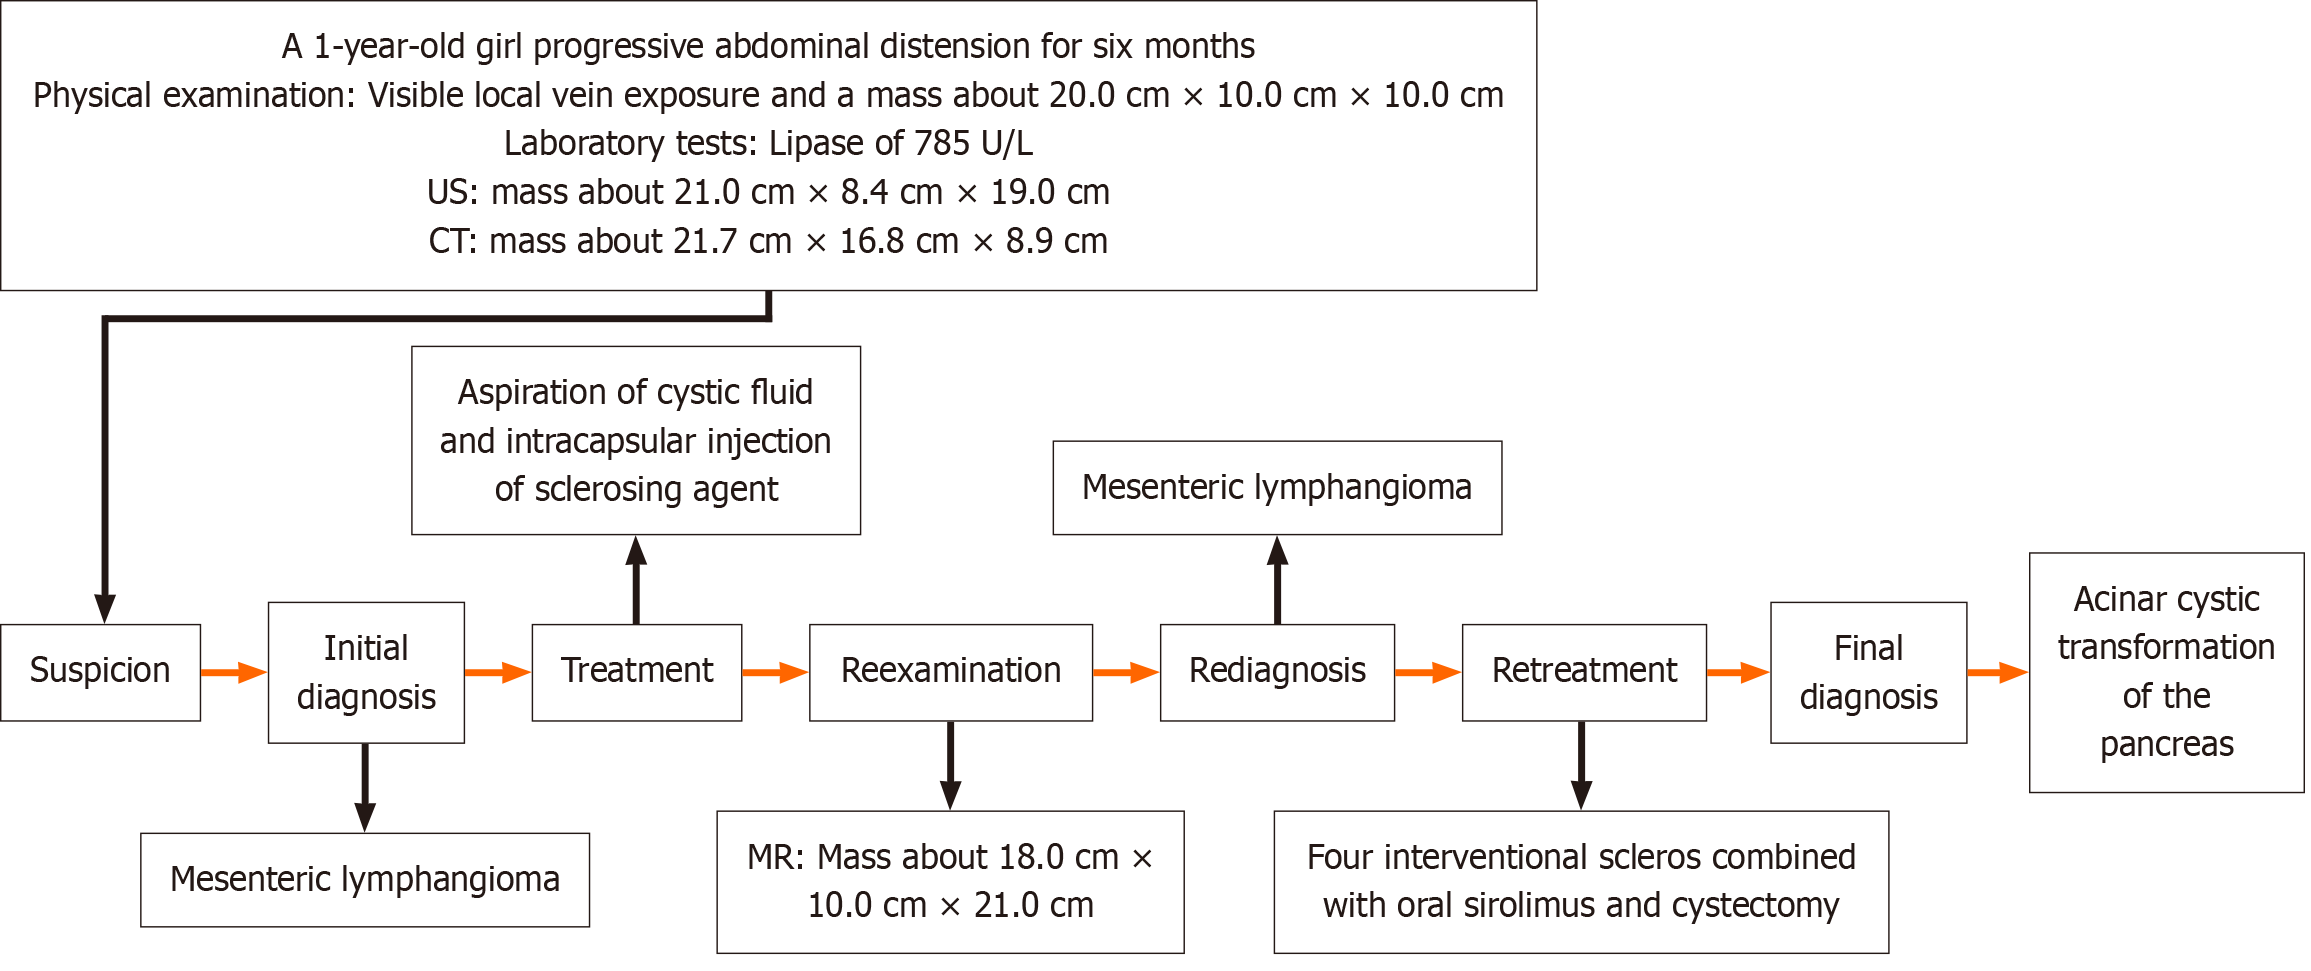

Figure 3 Diagnosis and treatment flow chart.

CT: Computed tomography; US: Ultrasound; MR: Magnetic resonance.